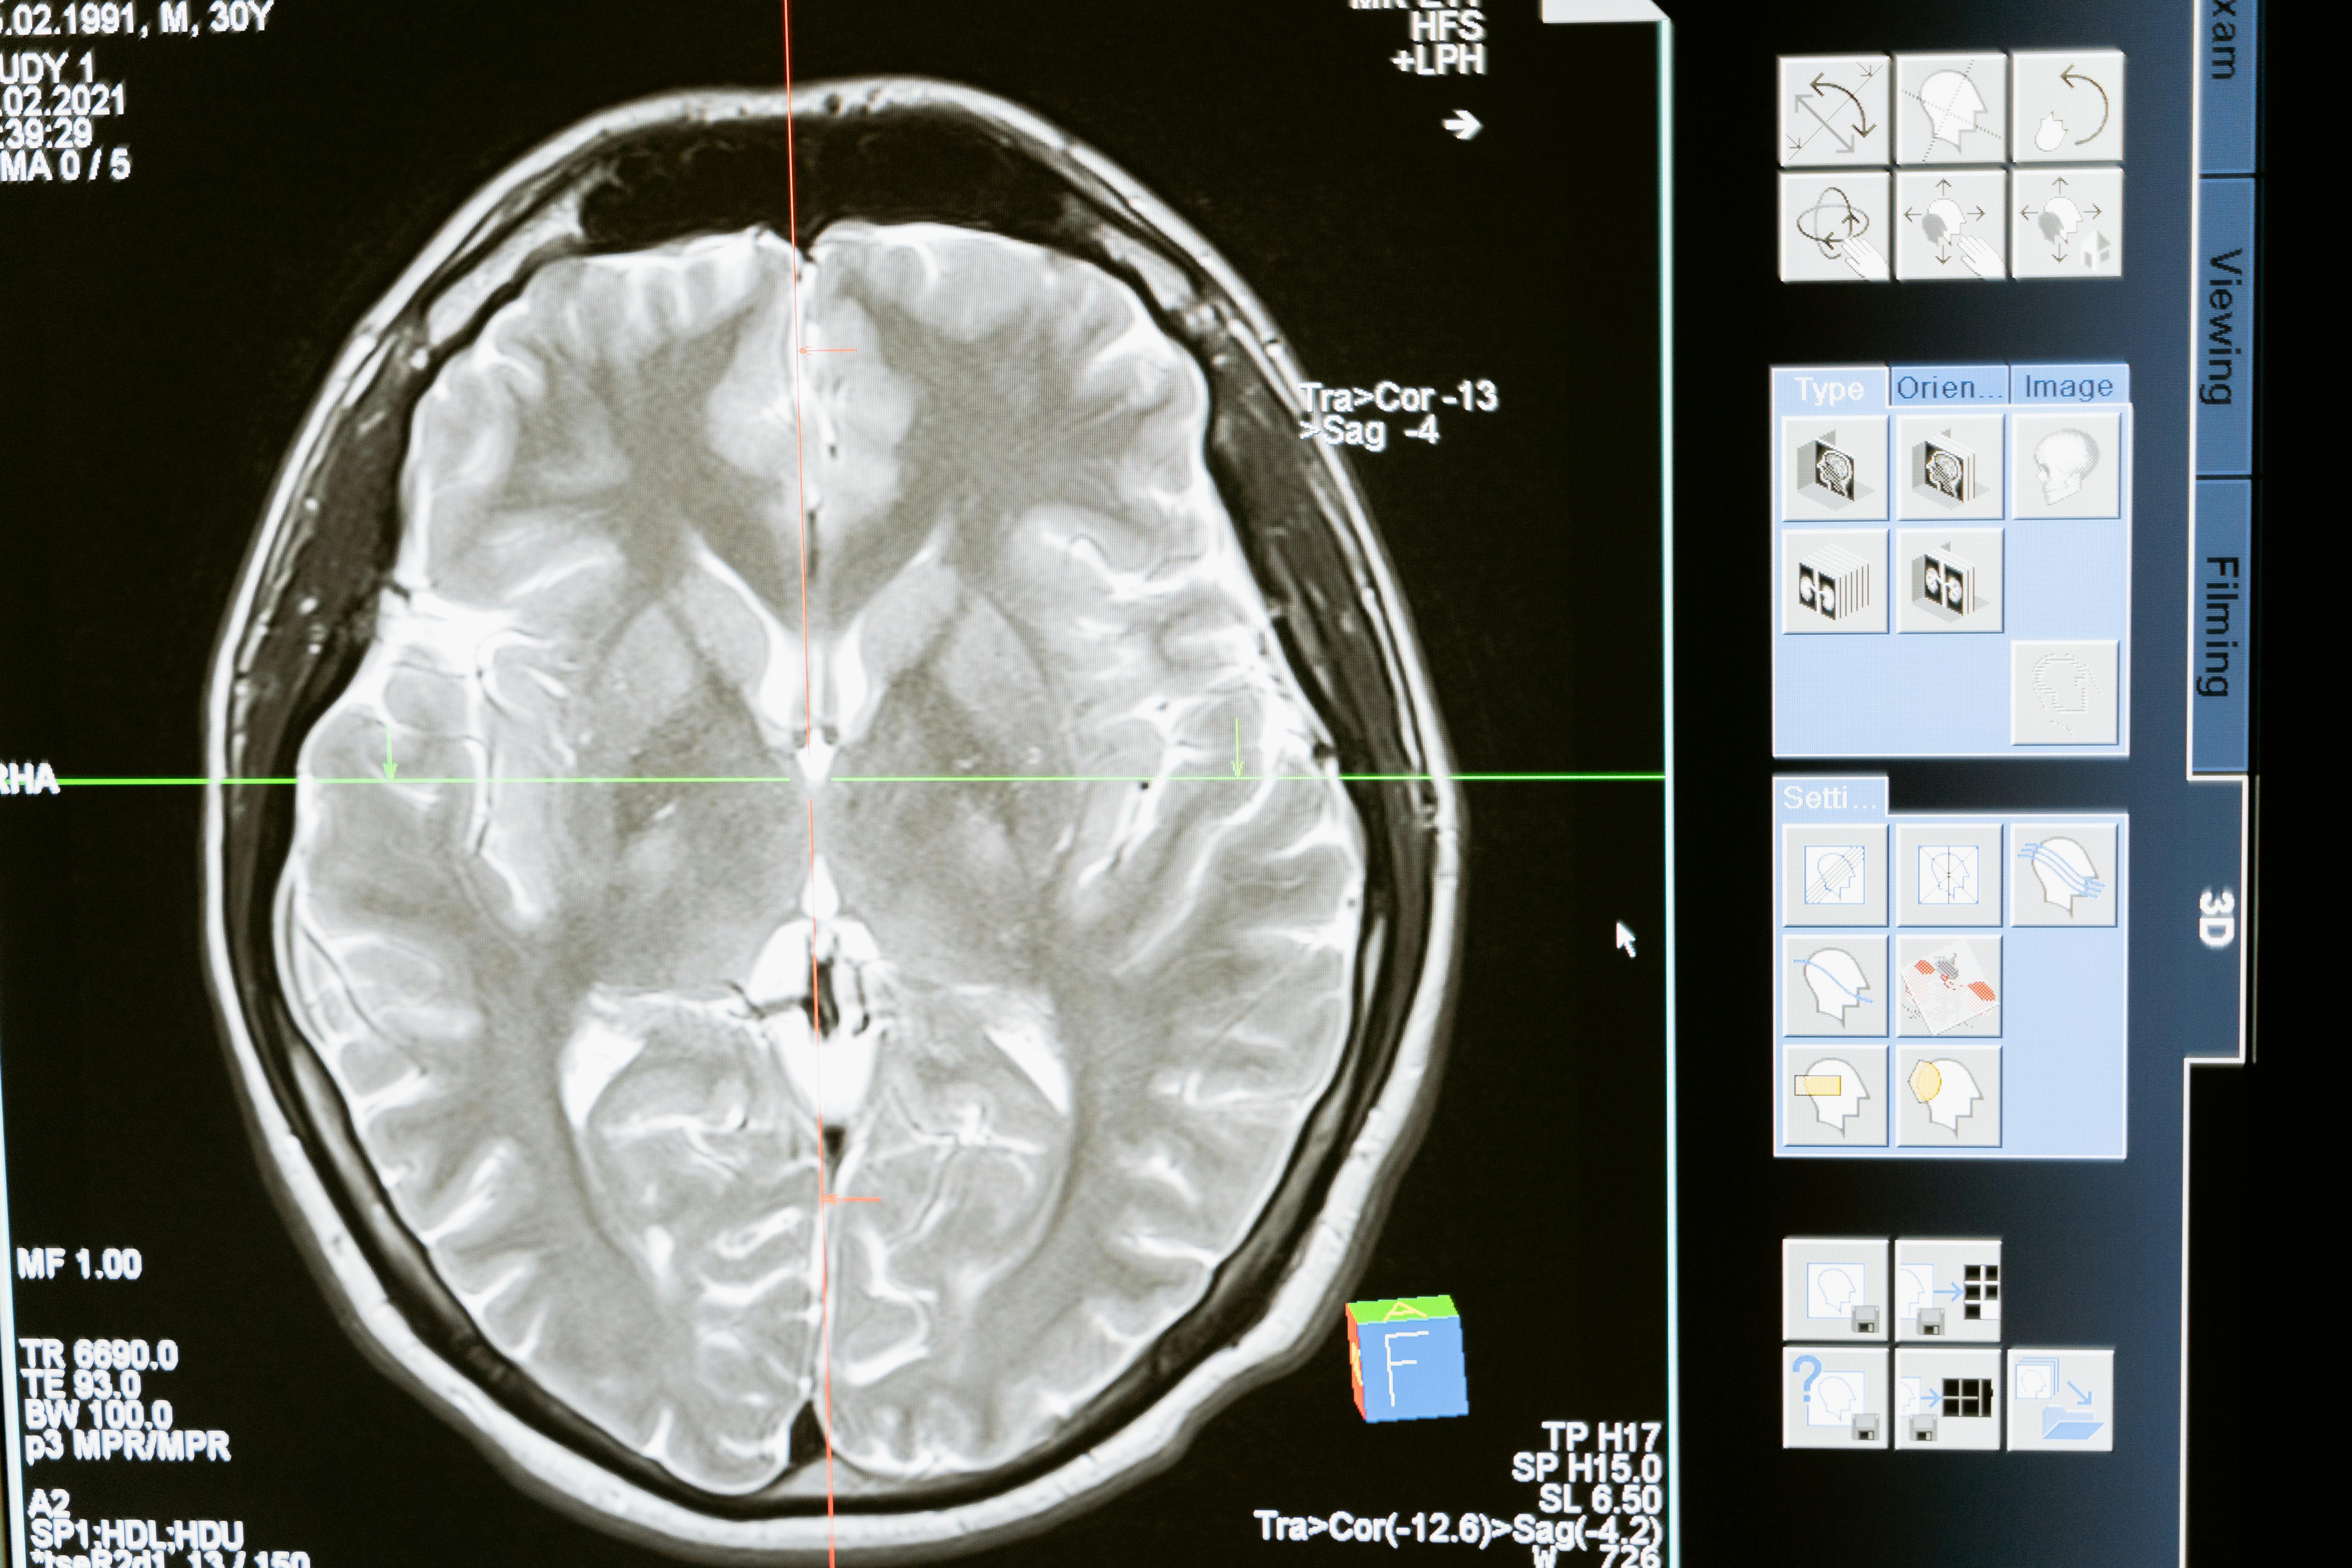

2. fMRI (Funksjonell magnetisk resonansavbildning)

Når Google lanserte sine mest ikoniske annonser, var det med en dyp forståelse av forbrukerens underbevisste preferanser, takket være fMRI. Denne teknologien gir bilder av hjernen som viser hvilke områder som aktiveres når folk ser på annonser, noe som gir innsikt i komplekse beslutningsprosesser.

- Gir detaljerte bilder av hjerneaktivitet, noe som gjør det mulig å forstå nøyaktig hva som skjer under reklameeksponering.

- Fanger opp dype emosjonelle og kognitive responser som er nøkkelen til å bygge sterke merkevarer.

Bruksområder: fMRI er ideelt for å forstå hvorfor visse annonser skaper dype forbindelser med forbrukerne, og hvorfor andre blir glemt like raskt som de vises.